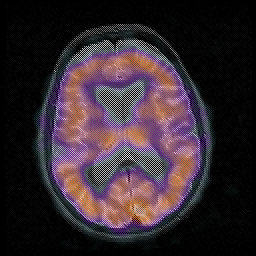

Huntington's Chorea, MR -- Slice #11

[Home][Help][Clinical] Slice 11